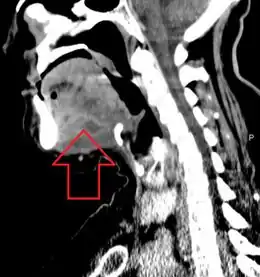

A CT scan of the neck with contrast material is used to identify deep neck space infections.[19] If there is suspicion of the infection of the chest cavity, a chest scan is sometimes done.[20] Infections originating in the roots of teeth can be identified with a dental X-ray.[21][20]